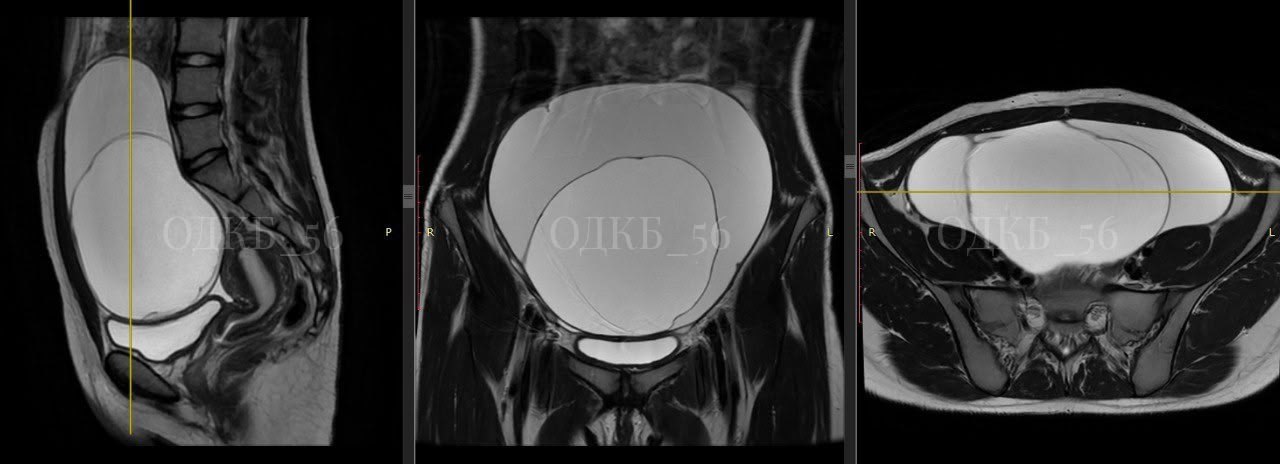

Пациентка поступила в экстренное отделение ОДКБ с сильными болями в животе. УЗИ и МРТ показали крупное образование.

Ей удалили муцинозную цистаденому яичника — доброкачественное образование диаметром около 20 сантиметров.

Фото: ОДКБ